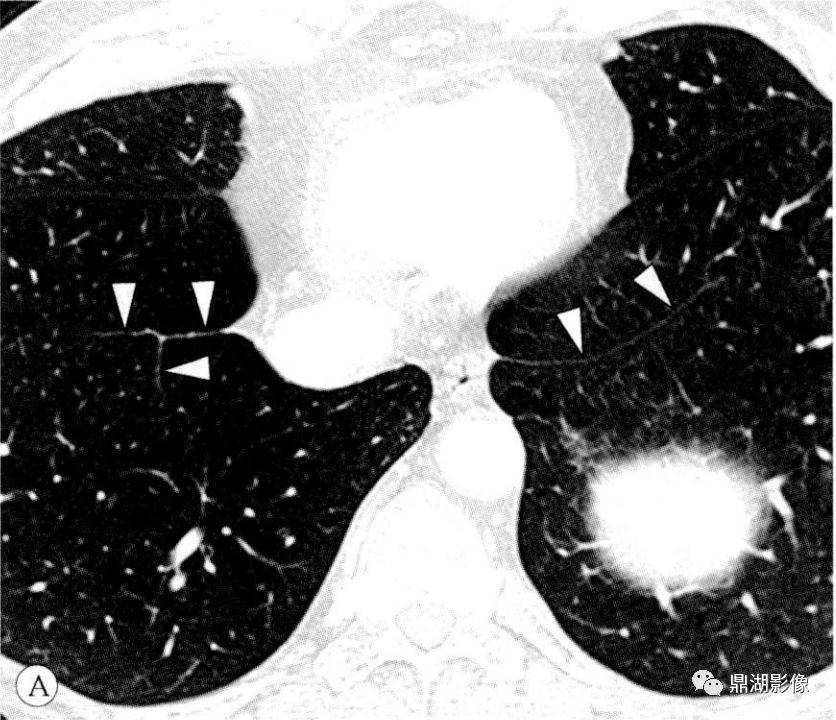

右下肺韧带-胸膜分布-胸部ct断层影 像-肺窗(三) 解剖图片

红色箭头所指处为两侧肺韧带白色箭头所指处为右下肺韧带小结当我们